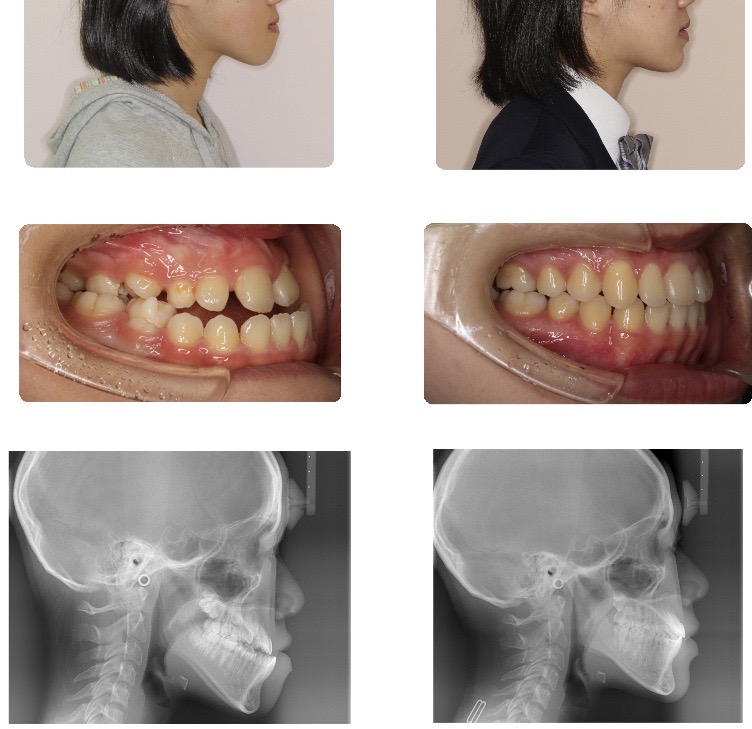

顎変形症(骨格性反対咬合)

下顎が前方に突出し、前歯が全く咬めない状態でした。

上下の顎の位置を合わせることで、前歯がしっかり咬み合った咬合に仕上がっています。前歯のみならず奥歯も上下でしっかりと咀嚼できるようになりました。

また下顎が後退したことで、顔貌的にも調和のとれた良好な側貌になりました。